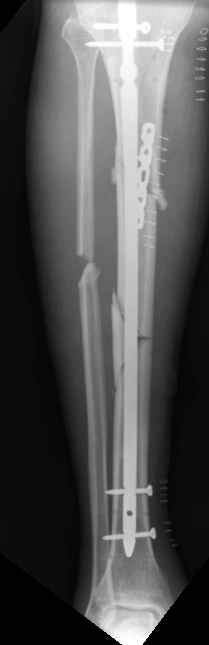

These can be challenging. I agree w/ all Dr. Carr's points. My preference to prevent the deformity is to use an anteromedial plate. See attached case.